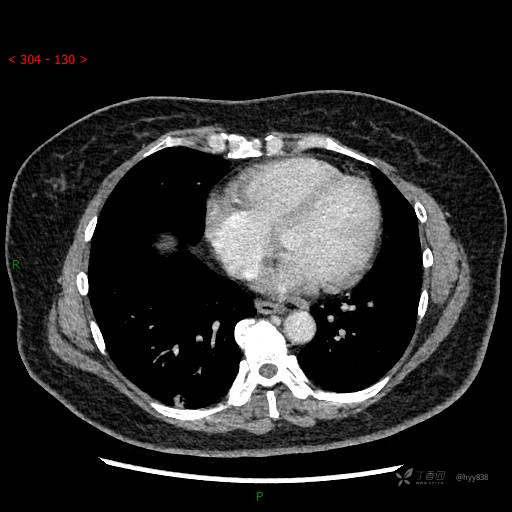

静脉期